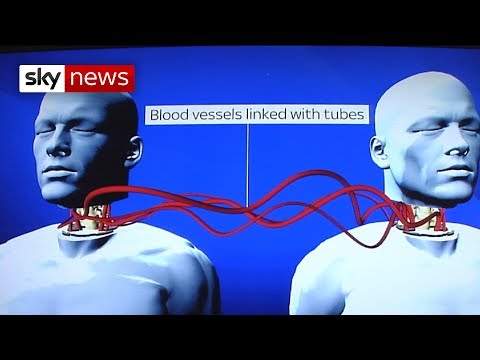

Head Transplant Machine – BrainBridge

World's First Head Transplant: What's Involved?

How These Crazy Head Transplants Machines Work